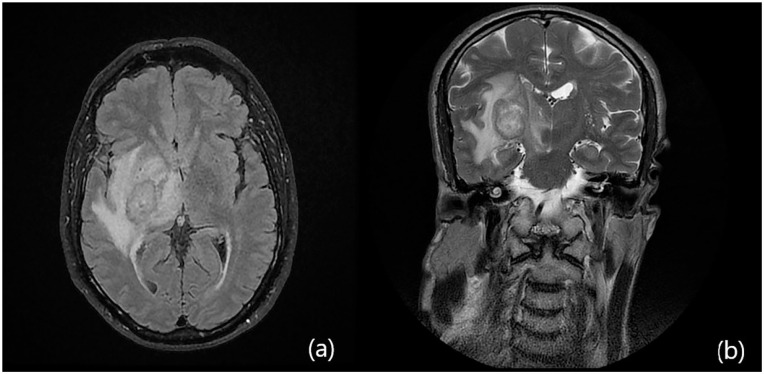

Case presentation: We describe the case of a north african 63-year-old man with an unremarkable medical history except for recent anti-SARS-CoV-2 vaccinations. Following the administration of a third anti-SARS-CoV-2 booster vaccine, the patient developed neurological symptoms, including left hemiparesis, facial palsy, vertigo, and balance issues. Imaging studies revealed a right temporo-parietal lesion consistent with intracranial suppuration. Stereotaxic cerebral biopsy confirmed the presence of purulent content, indicating a brain abscess caused by multi-sensitive streptococcus salivarius.